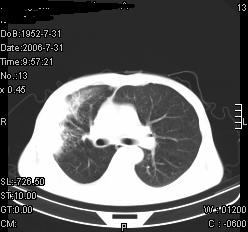

患者,男,54岁,咳嗦,咳痰20天。抗炎治疗2周。现esr76mm/h,目前患者症状明显好转,但发现两次ct片未见明显变化。两次分别做与7.25、7.31。第一次诊断右肺上叶炎症累计胸膜。大家看,从影像上内排除结核吗?

结核的可能性非常大,右上肺病变应该考虑干酪性肺炎。理由:

1.纵隔内多发淋巴结肿大。

2.esr76mm/h。

3.虽经抗炎治疗肺窗病灶有所吸收、减小,但纵隔窗病灶形态、密度、范围无明显变化。如果是单纯的大叶性肺炎,“抗炎治疗2周,目前患者症状明显好转”病灶应该基本消散了,至少也处于吸收消散期,密度变淡、范围变小。同时本病例所示其内的密度不均匀,见多发大小不一空洞样影也不符合大叶性肺炎吸收消散期表现。

病灶特点:片状 索条 结节混杂影,部分融合,密度不均,广泛累及相应胸膜.

临床治疗;二周未吸收.但症状好转.

多考虑:肺结核.